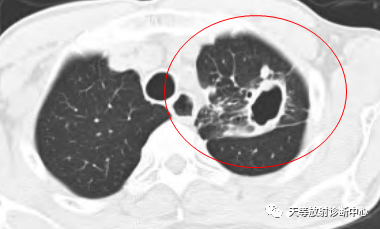

影像学表现:整体观察肺内多发病灶,散在分布,病灶的主要形态为:多发大小不等肺气囊、多发结节共同存在。

1、肺气囊大小不等,张力较大,圆形膨胀感强,周围可见大小不等结节影;

2、病灶主要沿支气管血管束方向分布,部分病灶达到胸膜下;

3、支气管间质增厚;

4、结节影大小不等,小的呈树芽征堆积,大的部分到达胸膜小,具有糊墙征,性格较温和。仔细观察病灶呈四边形、多边形,边缘刀切感,边界模糊。

首先感觉病变并不是非常的恶,偏向温和的病变。